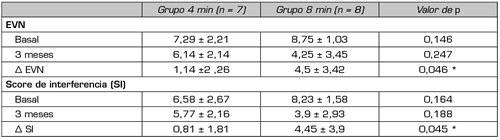

No encontramos ningún estudio que compare distintos esquemas de exposición a la RFP. En nuestro servicio se desarrolla actualmente un estudio prospectivo randomizado doble ciego en pacientes con dolor radicular lumbosacro refractario a los esteroides epidurales, utilizando como grupo control la aplicación del tiempo de exposición a la RFP que consideramos como estándar, esto es, 2 ciclos de 120 segundos (4 minutos) y como grupo de estudio, la aplicación de 4 ciclos de 120 segundos cada uno (8 minutos). Los resultados preliminares de los 15 pacientes realizados al momento (8 en el grupo de 8 minutos y 7 en el grupo control) muestran una disminución de la EVN y de la interferencia del dolor en las actividades diarias en ambos grupos, siendo las diferencias entre las evaluaciones basales y las realizadas a los 3 meses, mayores en el grupo de 8 minutos. A pesar del bajo tamaño de la muestra, estas diferencias alcanzaron significancia estadística (Surbano y Castromán, datos no publicados) (Tabla III). Esto indicaría un efecto analgésico más potente de la RFP cuando se aplica durante tiempos más prolongados, efecto que podría mantenerse por lo menos durante 3 meses después de la aplicación única del procedimiento.

Tabla III. Evaluación de la intensidad del dolor por escala verbal numérica (EVN) y de la interferencia del dolor en las actividades diarias (score de interferencia, si) utilizando el inventorio abreviado de dolor (brief pain inventory), en pacientes con dolor radicular lumbosacro unilateral, en los cuales se aplicó, en forma randomizada, 4 u 8 minutos de radiofrecuencia pulsada del ganglio de la raíz dorsal. La evaluación se hizo en condiciones basales y a los 3 meses, se presentó también las diferencias entre los valores basales y a los 3 meses (Δ EVN y Δ SI)